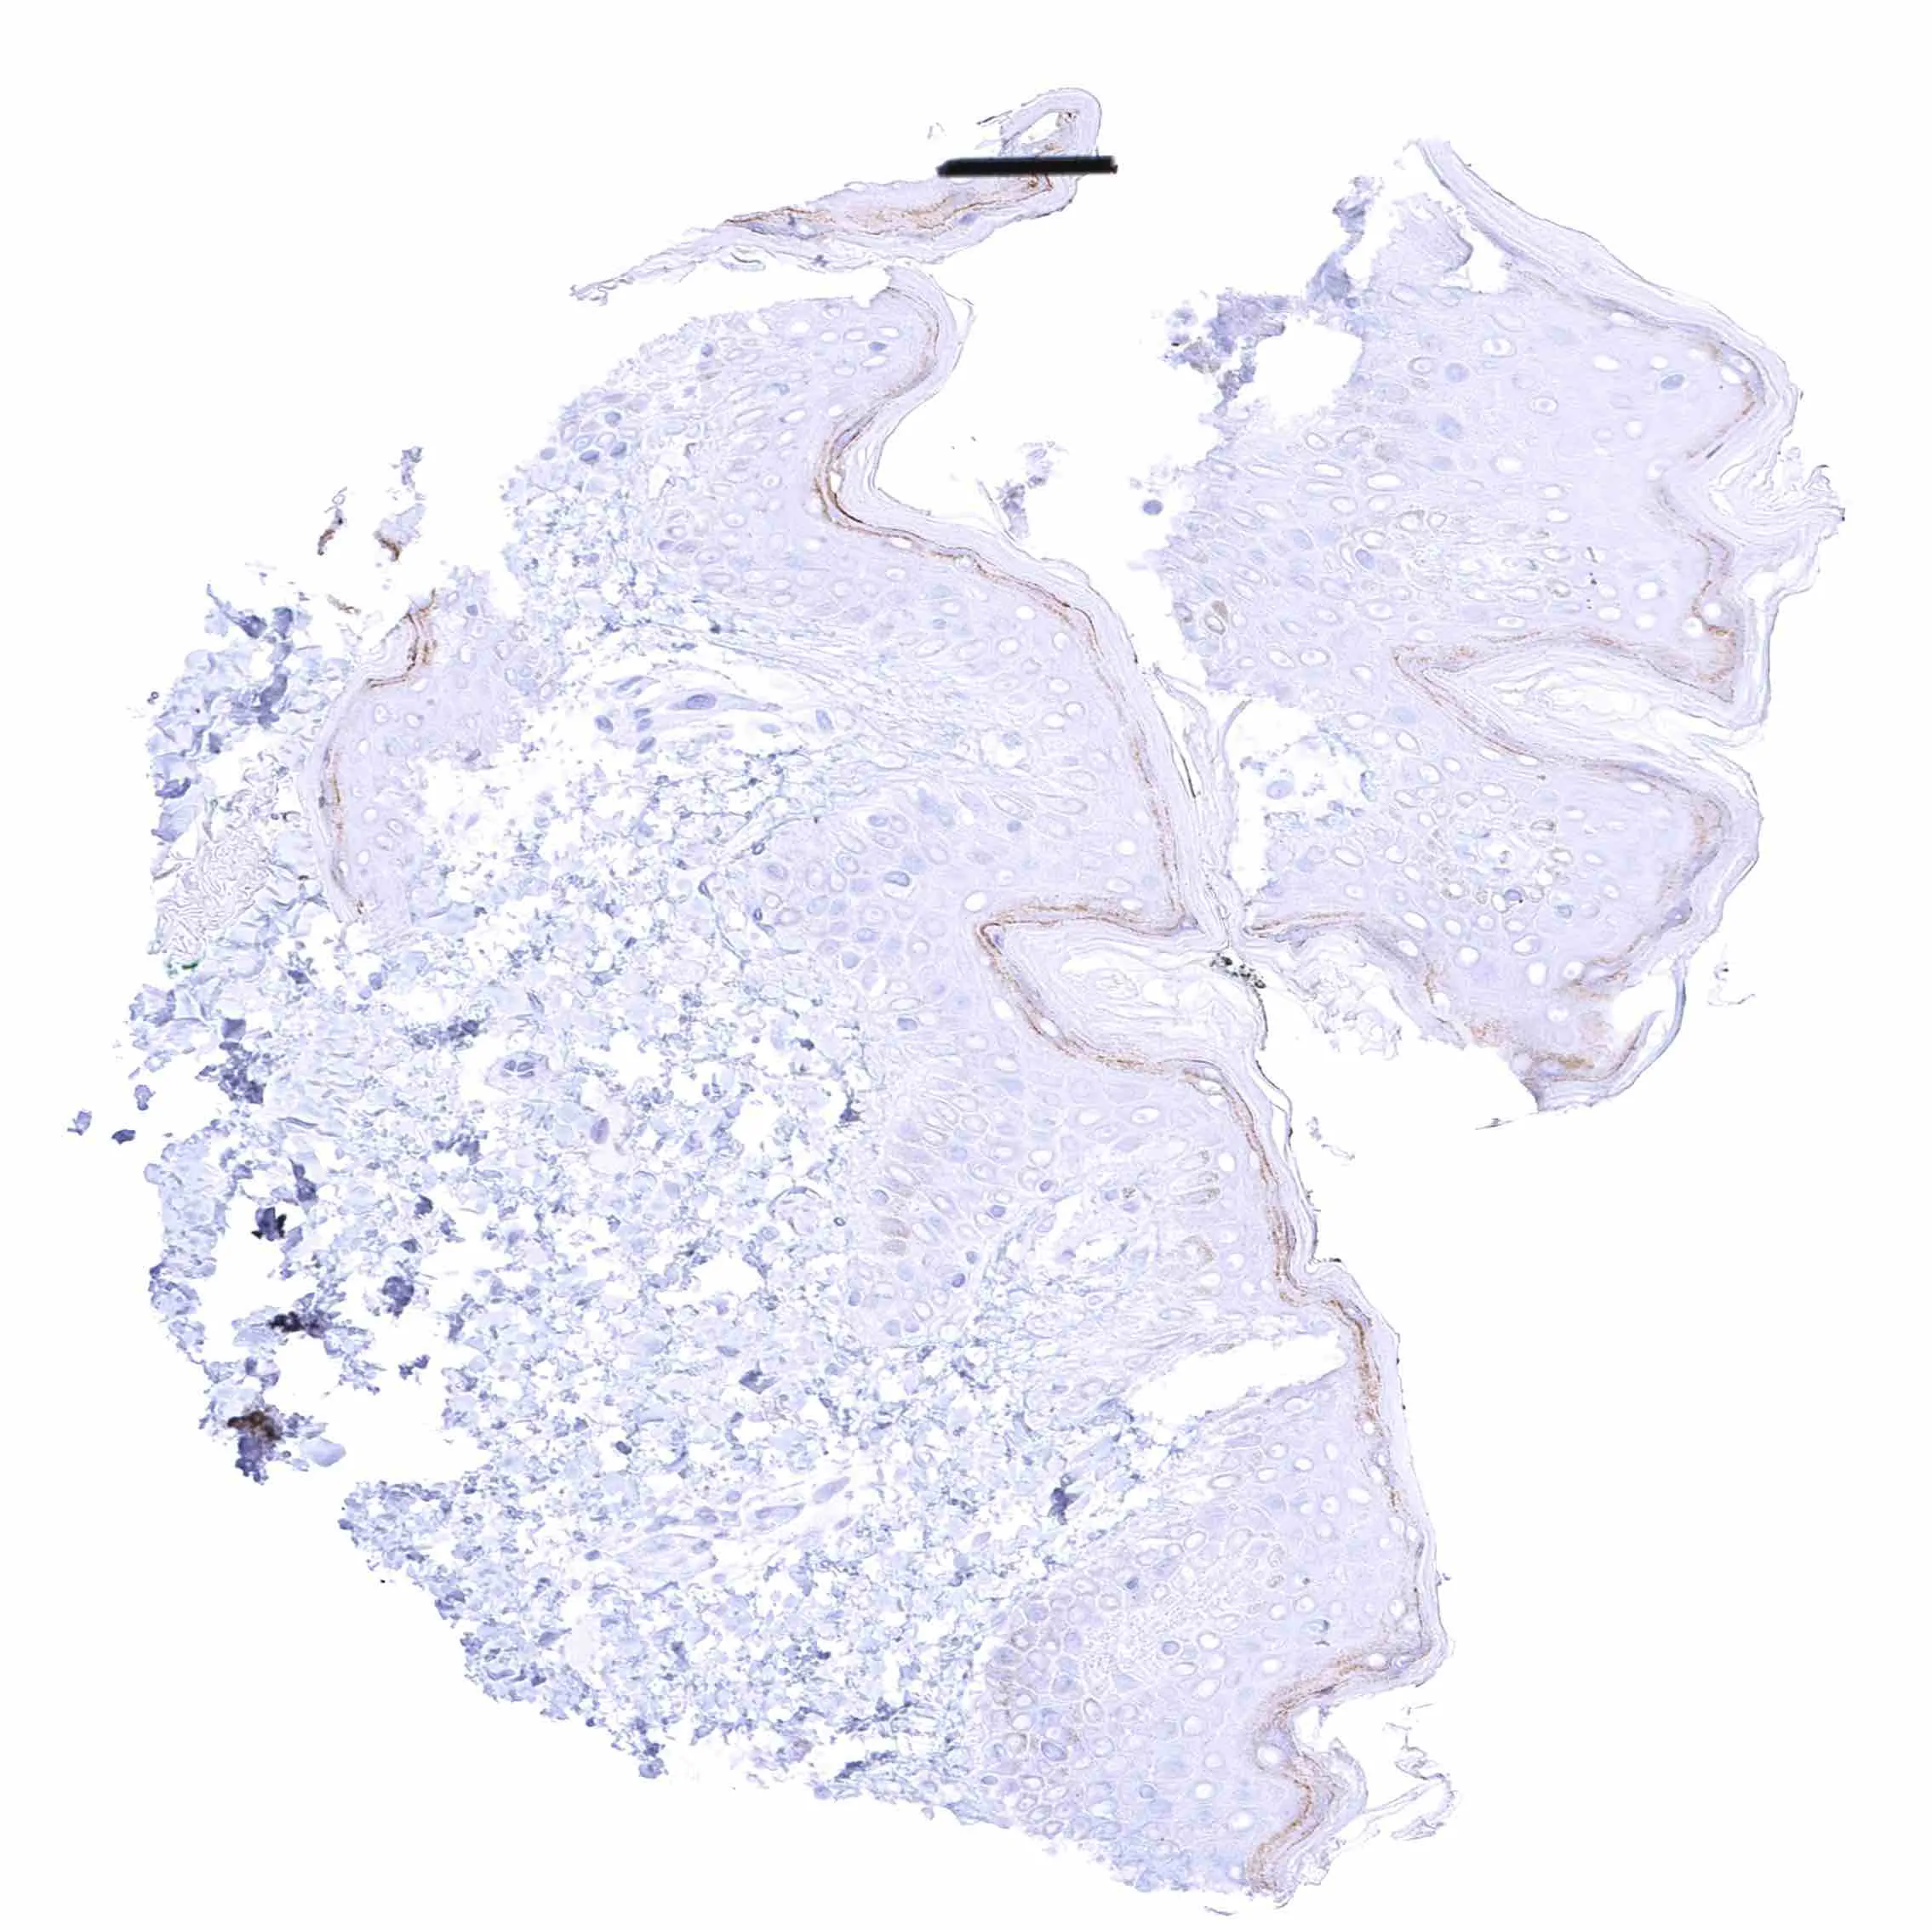

Skin – Distinct EGFRvIII staining of the granular layer of keratinizing squamous epithelium.